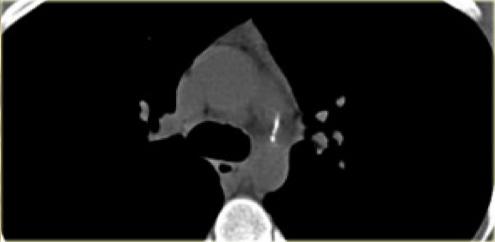

On the left a patient with a right arch with an aberrant left subclavian (indicated by the yellow arrow).

Scroll through the images on the left.

Again you have to realize that the axial CT-images have a ‘view from feet’.

There is a right arch and the left subclavian artery is the last branch of the aortic arch, indicating that this is an aberrant left subclavian.

Medially to the left subclavian artery we see the left common carotid, that originates from the right side and has an oblique course to the left.

The yellow arrow indicates the azygos vein.

The green arrow indicates the left superior intercostal vein, a normal variant, that we will discuss later.